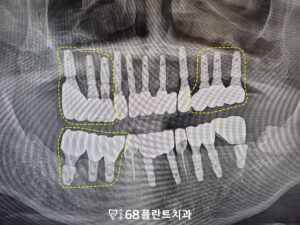

위 환자분은

전체적으로 치아가 안 좋은 거 같다며

철산역치과 이편한68플란트에

내원해 주셨습니다.

확인해 보니,

치주질환으로 인해

잇몸뼈가 소실되어 흔들리고

뿌리가 드러난 치아도 있었는데요.

해당 치아들은 살려서 쓴다고 해도

예후가 좋지 않아

장기적으로 안정적인 기능을

기대하기 어려운 상황이었습니다.

따라서, 발치와

임플란트 치료가 필요했습니다.

또한 기존 임플란트를

보철물들의 마모나

손상이 보였습니다.

이로 인해 임플란트의

기능이 저하되고,

미적 측면에서도 문제가

발생할 수 있었습니다.

따라서, 기존 보철물의 상태를 고려해

재보철이 필요했습니다.